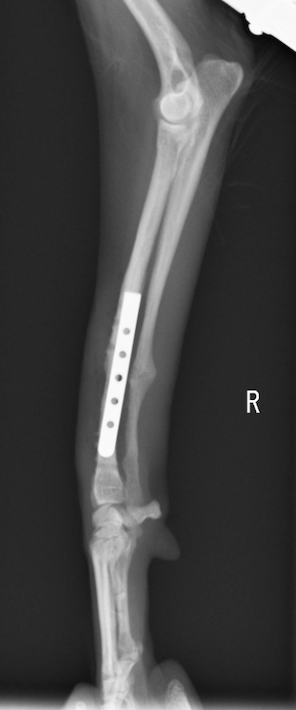

今回のワンちゃんも手術の決断をしてくださり、無事骨折した骨は、元通りのまっすぐな足の角度に治りました!

当グループの骨折手術は初回手術(1回目の手術のこと)であれば100%治っております。他の病院で一度手術してから再手術の場合、すでに癒合不全が起こっていると当然手術は難しくなります。癒合不全の手術は1回で治らないこともあります。

それほどに1回目の手術がとても大事になります。当グループでは骨折の専門家がおり確実な手術を希望される方が、紹介されて来院しております。骨折をしてしまったら、、、是非当院へ相談いただければと思います。